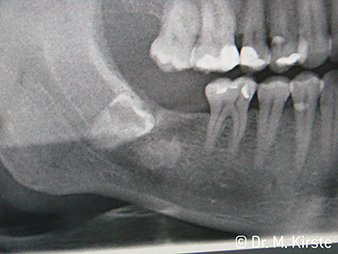

Con la rimozione dei denti del giudizio, gli strumenti chirurgici si spingono verso i limiti anatomici: la guancia ostacola i manipoli quando l'apertura orale è ridotta. O quando il molare distale rende più difficile l'accesso della fresa del contrangolo. In entrambi i casi, i nuovi contrangolo chirurgici di W&H offrono una soluzione intelligente, anche quando le separazioni dentali in zona apicale sono ampie.

Per la prima volta, gli strumenti di trasmissione WS-91 e WS-91 L G combinano i vantaggi dei manipoli e dei contrangolo chirurgici (figura 1). Sul lato anteriore, l'angolo ampliato tra l'area di presa e l'asse di foratura consente un accesso ottimale alla zona buccale e occlusale, sopra la fila di denti (figura 4). I denti malposizionati possono essere separati con semplicità (figure 6 e 7). Inoltre, la visuale della persona addetta al trattamento sull'area di intervento è notevolmente migliore rispetto agli strumenti disponibili in passato. Ecco l'opinione del dott. Mario Kirste di Francoforte sull'Oder: "Quando ruoto leggermente la testina del contrangolo, posso lavorare in modo particolarmente sicuro e rapido nell'area retromolare. Lo strumento ha il potenziale per conciliare gli schieramenti contrapposti di chi usa i contrangolo e chi usa i manipoli.“ (figure 2 - 5)

Un ulteriore campo di utilizzo dei contrangolo WS-91 e WS-91 L G è la resezione di apici radicolari. Anche con i molari dell'arcata superiore e quando l'apertura orale è ridotta, l'ergonomia dello strumento consente un'ottima visuale. Con il WS-91 L G viene fornito anche un Mini-LED+, che illumina a giorno l'area di trattamento. Il Dott. Kirste afferma: "I nuovi contrangolo rappresentano una transizione davvero riuscita. La straordinaria efficienza tecnica degli strumenti W&H amplia le mie vedute e le mie possibilità negli interventi di chirurgia quotidiani."